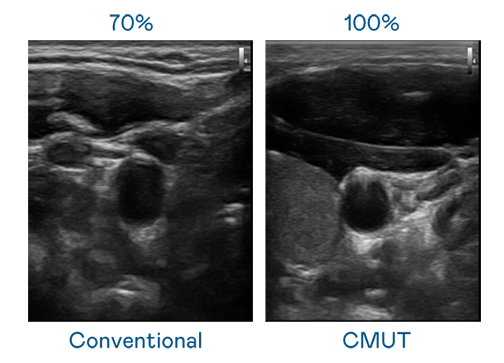

CMUT ¼¼ÊõÊÇÒ»ÖÖÓõçÈÝʽ΢»úµçÔª¼þÀ´²úÉú³¬Òô²¨Ñ¶ºÅµÄ¼¼Êõ¡£Ó봫ͳ PZT ѹµçʽ¼¼ÊõÏà±È£¬CMUT Ƶ¿íÔö¼Ó 30%£¬¸ü¿íƵµÄ³¬Òô²¨Ñ¶ºÅÈÃÓ°Ïñ½âÎö¶È´ó·ùÌáÉý£¬ÊÇʵÏÖ¸ßÓ°ÏñÆ·ÖÊÒ½ÁƳ¬Òô²¨É¨Ãè¡¢´Ù½ø¾«×¼Ò½ÁÆ·¢Õ¹µÄ¹Ø¼ü¼¼Êõ¡£

³¬Òô²¨Ó°ÏñµÄ½âÎö¶È¸ßµÍ£¬Ê×ÏÈÈ¡¾öÓÚ̽ͷÄÜ·¢³öµÄѶºÅƵ¿í¡£evoÊÓѶ CMUT ¿ÉÌṩ¸ßÇåÎúµÄ³¬Òô²¨Ñ¶ºÅ£¬Ìṩ¸ßƵ¿í¡¢¸ßÁéÃô¶È¡¢Ó°ÏñÎÆÀíϸ½Ú¸ü¸ßµÄ³¬Òô²¨Ó°Ïñ£¬ÐÖúÒ½»¤ÈËÔ±Ëõ¶ÌÓ°ÏñÅжÁʱ¼ä¼°ÀûÓþ«×¼µÄÒ½ÁÆÓ°Ïñ½øÐÐÕï¶Ï¡£